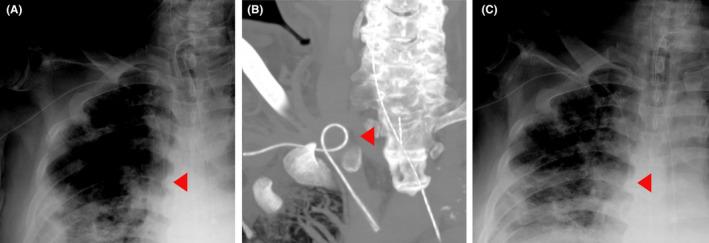

Self-correction of a migrated power-injectable peripherally inserted central catheter following contrast-enhanced computed tomography.

The use of power-injectable peripherally inserted central catheter (PIPICC) is a common practice, but displacement of these lines following injection of contrast media has been reported in 15.4% of cases. This report presents imaging evidence of displacement and self-correction of a PIPICC line following contrast-enhanced computed tomography.